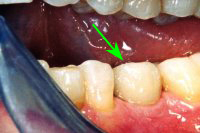

Ein aus der Kindheit stammender Milchzahn ohne Wurzeln im Seitenzahngebiet (Abb. 1), der eiterte und gezogen werden musste, hinterliess bei einer 37 Jahre alten Patientin eine grosse Lücke, aber gesunde Nachbarzähne. Um die Lücke mit einem festsitzenden Zahnersatz zu schliessen, setzen wir ein Zahnimplantat (Abb. 2 und 3). Das Setzen einer Zahnbrücke wäre ebenfalls möglich gewesen, hätte aber das Beschleifen der gesunden Nachbarzähne erfordert, was wir vermeiden wollten.

Sechs Wochen später, nach Einheilung des Implantates (Abb. 2), wird ein Aufbau aus Titan ins Implantat geschraubt (Abb. 3). Nach Abdrucknahme fertigt der Zahntechniker eine Krone an (in diesem Fall eine Vollporzellankrone), die auf dem Implantatpfosten einzementiert wird (Abb. 4). In Abb. 5 ist das Schlussröntgenbild zu sehen.